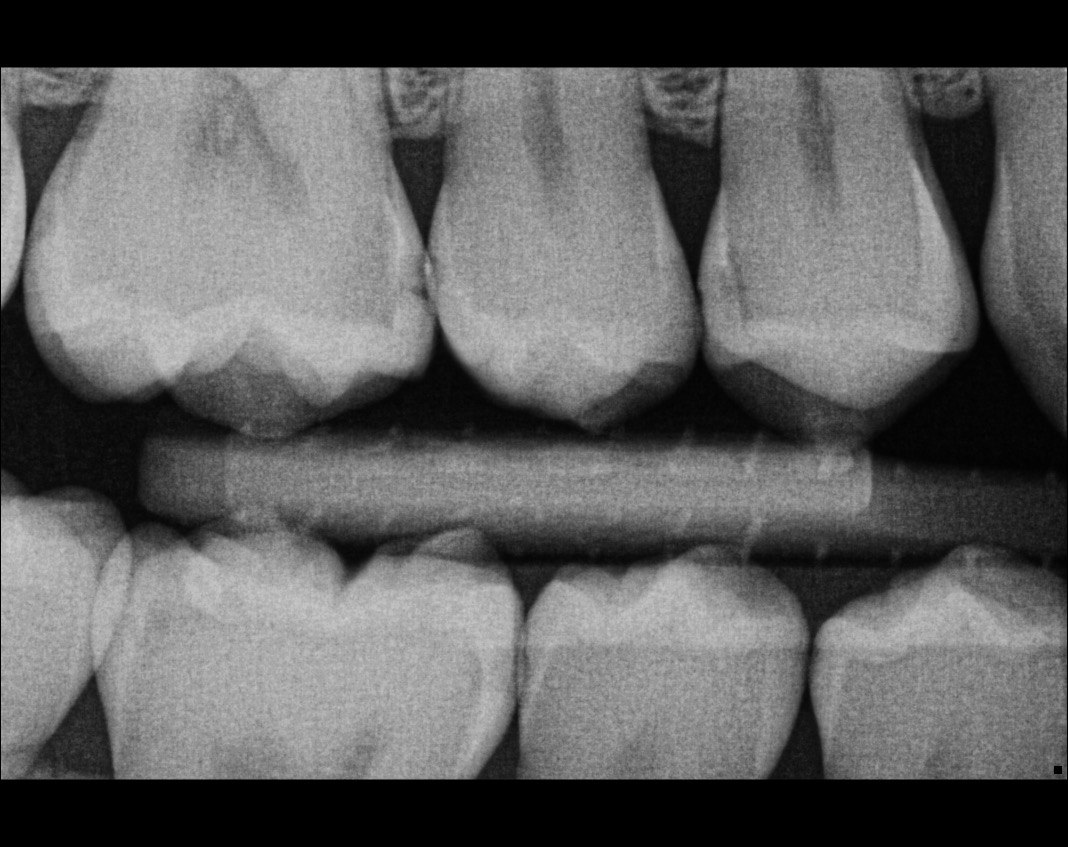

Question 7: What are the options associated with the distal surface of the tooth # 2.1 and mesial surface of the tooth # 2.2 respectively?

Question 8: What is the condition associated with the occlusal surface of the tooth # 1.6?

Question 9: What is the condition associated with the mesial and distal surfaces of the tooth # 1.4 respectively?

Question 10: What is the condition of the distal surfaces of the teeth # 1.5 and 1.6 respectively?